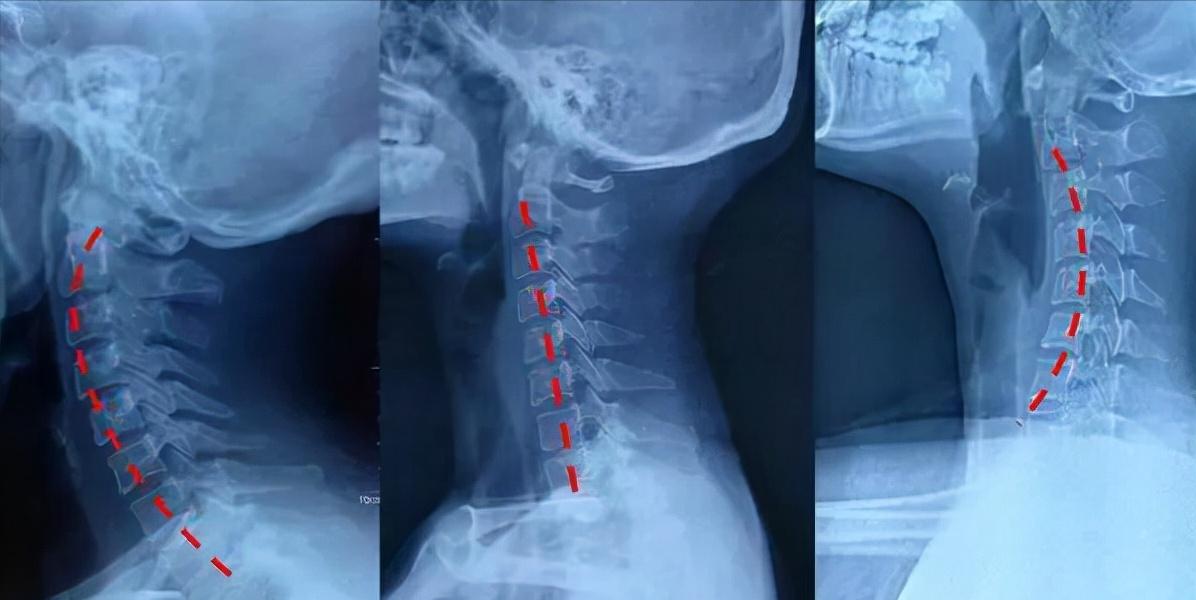

由上图可以看出,为了保持良好的生理曲度。枕头一定是要与身体有比较好的贴合度,另外。如果枕头过高、过软有可能导致生理曲度变直、反弓。但是如果枕头过硬,虽然保持了支撑力,但是舒适度又会大大降低。所以说,选择一款合适自己的枕头,非常有必要。

从上图可以看出,如果 枕头过高 ,颈椎一直处于受压状态,对于白天习惯做“低头族”的我们,晚上颈椎也得不到舒展。如果去掉枕头的话,头部又得不到合适的支撑。